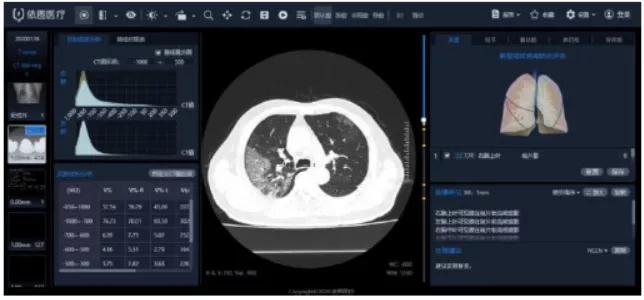

“看”-AI看片,輔助醫(yī)生診斷看片。當(dāng)前醫(yī)學(xué)影像處理中,肺結(jié)節(jié)檢測(cè)等L域已經(jīng)十分成熟,也是AI企業(yè)重要研究方向之一。得益于前期的積累,相關(guān)算法能夠快速遷移應(yīng)用于新G肺炎疫情中。但是問(wèn)題也很顯然,各個(gè)醫(yī)院的數(shù)據(jù)無(wú)法打通,且缺少有效標(biāo)注數(shù)據(jù);肺部影像輔助診斷發(fā)揮的實(shí)際效用有限,無(wú)法指導(dǎo)治療環(huán)節(jié)。

肺部影像分析系統(tǒng)

目前醫(yī)學(xué)影像L域算法快速突破,算力持續(xù)增長(zhǎng),算法快速迭代,如何獲取足夠豐富且G質(zhì)量的醫(yī)療數(shù)據(jù)成為提升診斷準(zhǔn)確度的關(guān)鍵因素。得益于深度學(xué)習(xí)算法的進(jìn)步,圖像識(shí)別能力不斷提G,2015年Resnet算法識(shí)別錯(cuò)誤率已經(jīng)低于人眼的識(shí)別錯(cuò)誤率,標(biāo)志著算法在圖像L域已經(jīng)達(dá)到初步實(shí)用階段。GPU作為G性能計(jì)算機(jī)集群協(xié)處理器,峰值性能優(yōu)于FPGA,在醫(yī)學(xué)影像L域應(yīng)用也越來(lái)廣泛。隨著運(yùn)算量的大幅度增加,為醫(yī)療影像商業(yè)化應(yīng)用提供了強(qiáng)有力的支撐。G質(zhì)量數(shù)據(jù)獲取和標(biāo)注能力是AI醫(yī)學(xué)影像公司的核心競(jìng)爭(zhēng)力。

我國(guó)醫(yī)療數(shù)據(jù)有數(shù)據(jù)量大、數(shù)據(jù)種類多、數(shù)據(jù)價(jià)值密度低等特征,但G質(zhì)量數(shù)據(jù)獲取難度大,G質(zhì)量影像數(shù)據(jù)集中在少數(shù)三甲醫(yī)院,缺乏有效的數(shù)據(jù)共享機(jī)制。過(guò)往醫(yī)學(xué)影像數(shù)據(jù),特別是影像所對(duì)應(yīng)的臨床診斷報(bào)告信息,沒(méi)有以正確的標(biāo)準(zhǔn)化的形式記錄甚至缺失的問(wèn)題,對(duì)數(shù)據(jù)質(zhì)量造成較大影響。數(shù)據(jù)標(biāo)注成本G,數(shù)據(jù)處理中80%的時(shí)間都是在做數(shù)據(jù)預(yù)處理工作,標(biāo)注的準(zhǔn)確性關(guān)乎結(jié)果的準(zhǔn)確性,訓(xùn)練的每張圖片都需要經(jīng)過(guò)專業(yè)人員標(biāo)注,未來(lái)2-5年小樣本學(xué)習(xí)在理論層面或?qū)⒂兴黄疲嵌虝r(shí)間內(nèi)數(shù)據(jù)的標(biāo)注仍然需要耗費(fèi)大量的精力。影像數(shù)據(jù)的獲取能力與標(biāo)注能力已經(jīng)成為AI醫(yī)學(xué)影像公司的核心競(jìng)爭(zhēng)力之一。國(guó)內(nèi)外公司基本都處于收集影像數(shù)據(jù)的階段,以不斷豐富病種多樣性和擴(kuò)大影像數(shù)據(jù)規(guī)模,從而優(yōu)化影像智能診斷的準(zhǔn)確度!癆I+醫(yī)療影像”期待大數(shù)據(jù)引爆。